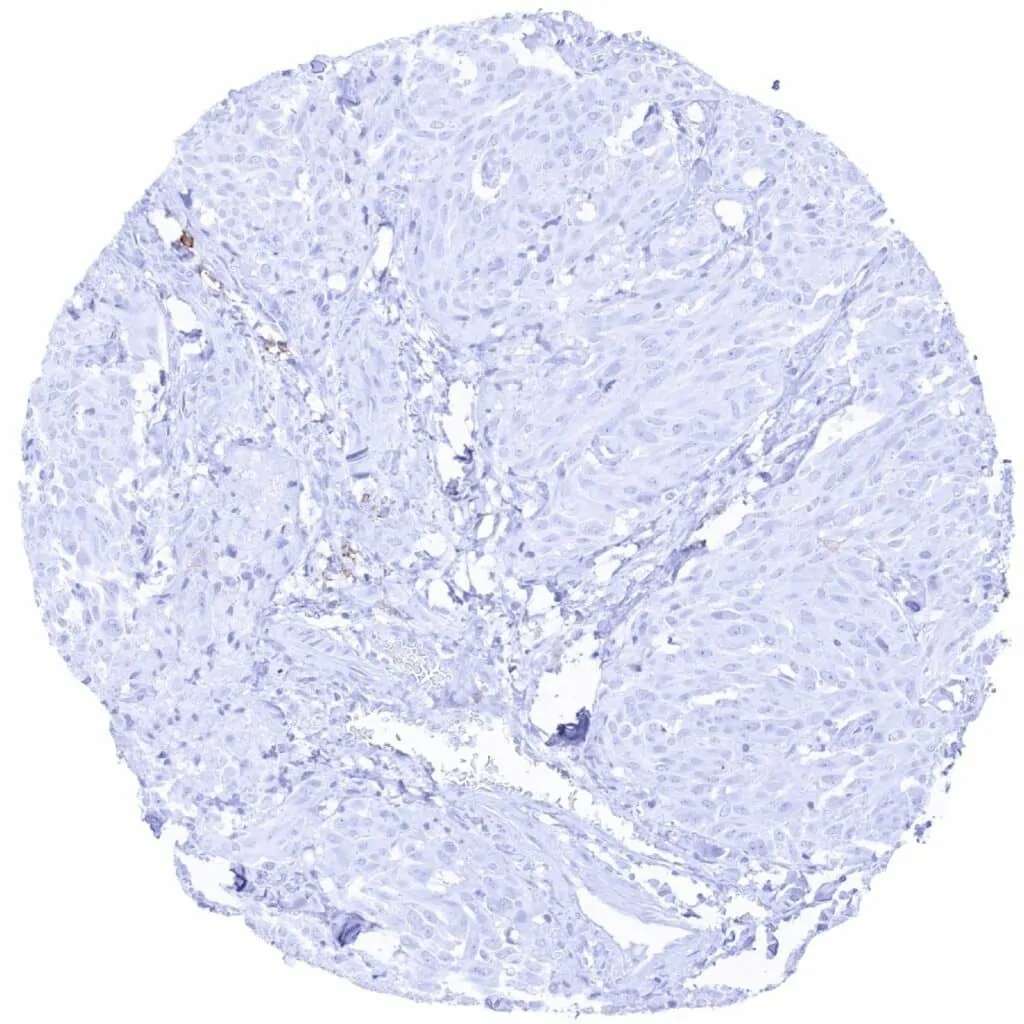

Larynx – CD38 negative squamous cell carcinoma